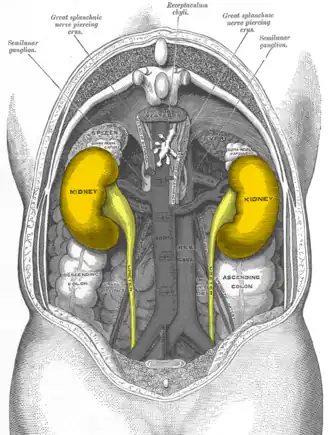

Почки — органы бобовидной формы, размерами 10-12 см в длину, 5-6 см в ширину и 3-4 см в толщину[1], располагающиеся в забрюшинном пространстве, вблизи поясничного отдела позвоночника. Почки окружены перинефральным жиром; кверху и несколько спереди от почек располагаются надпочечники. Кровоток в почках осуществляется через почечные артерии (ветви брюшной аорты) и составляет 1,25 л/мин (25 % от сердечного кровотока). Это является важным аспектом в связи с тем, что основной ролью почек является фильтрация из крови ненужных веществ. Почечные лоханки продолжаются книзу мочеточниками, спускающимися к мочевому пузырю.